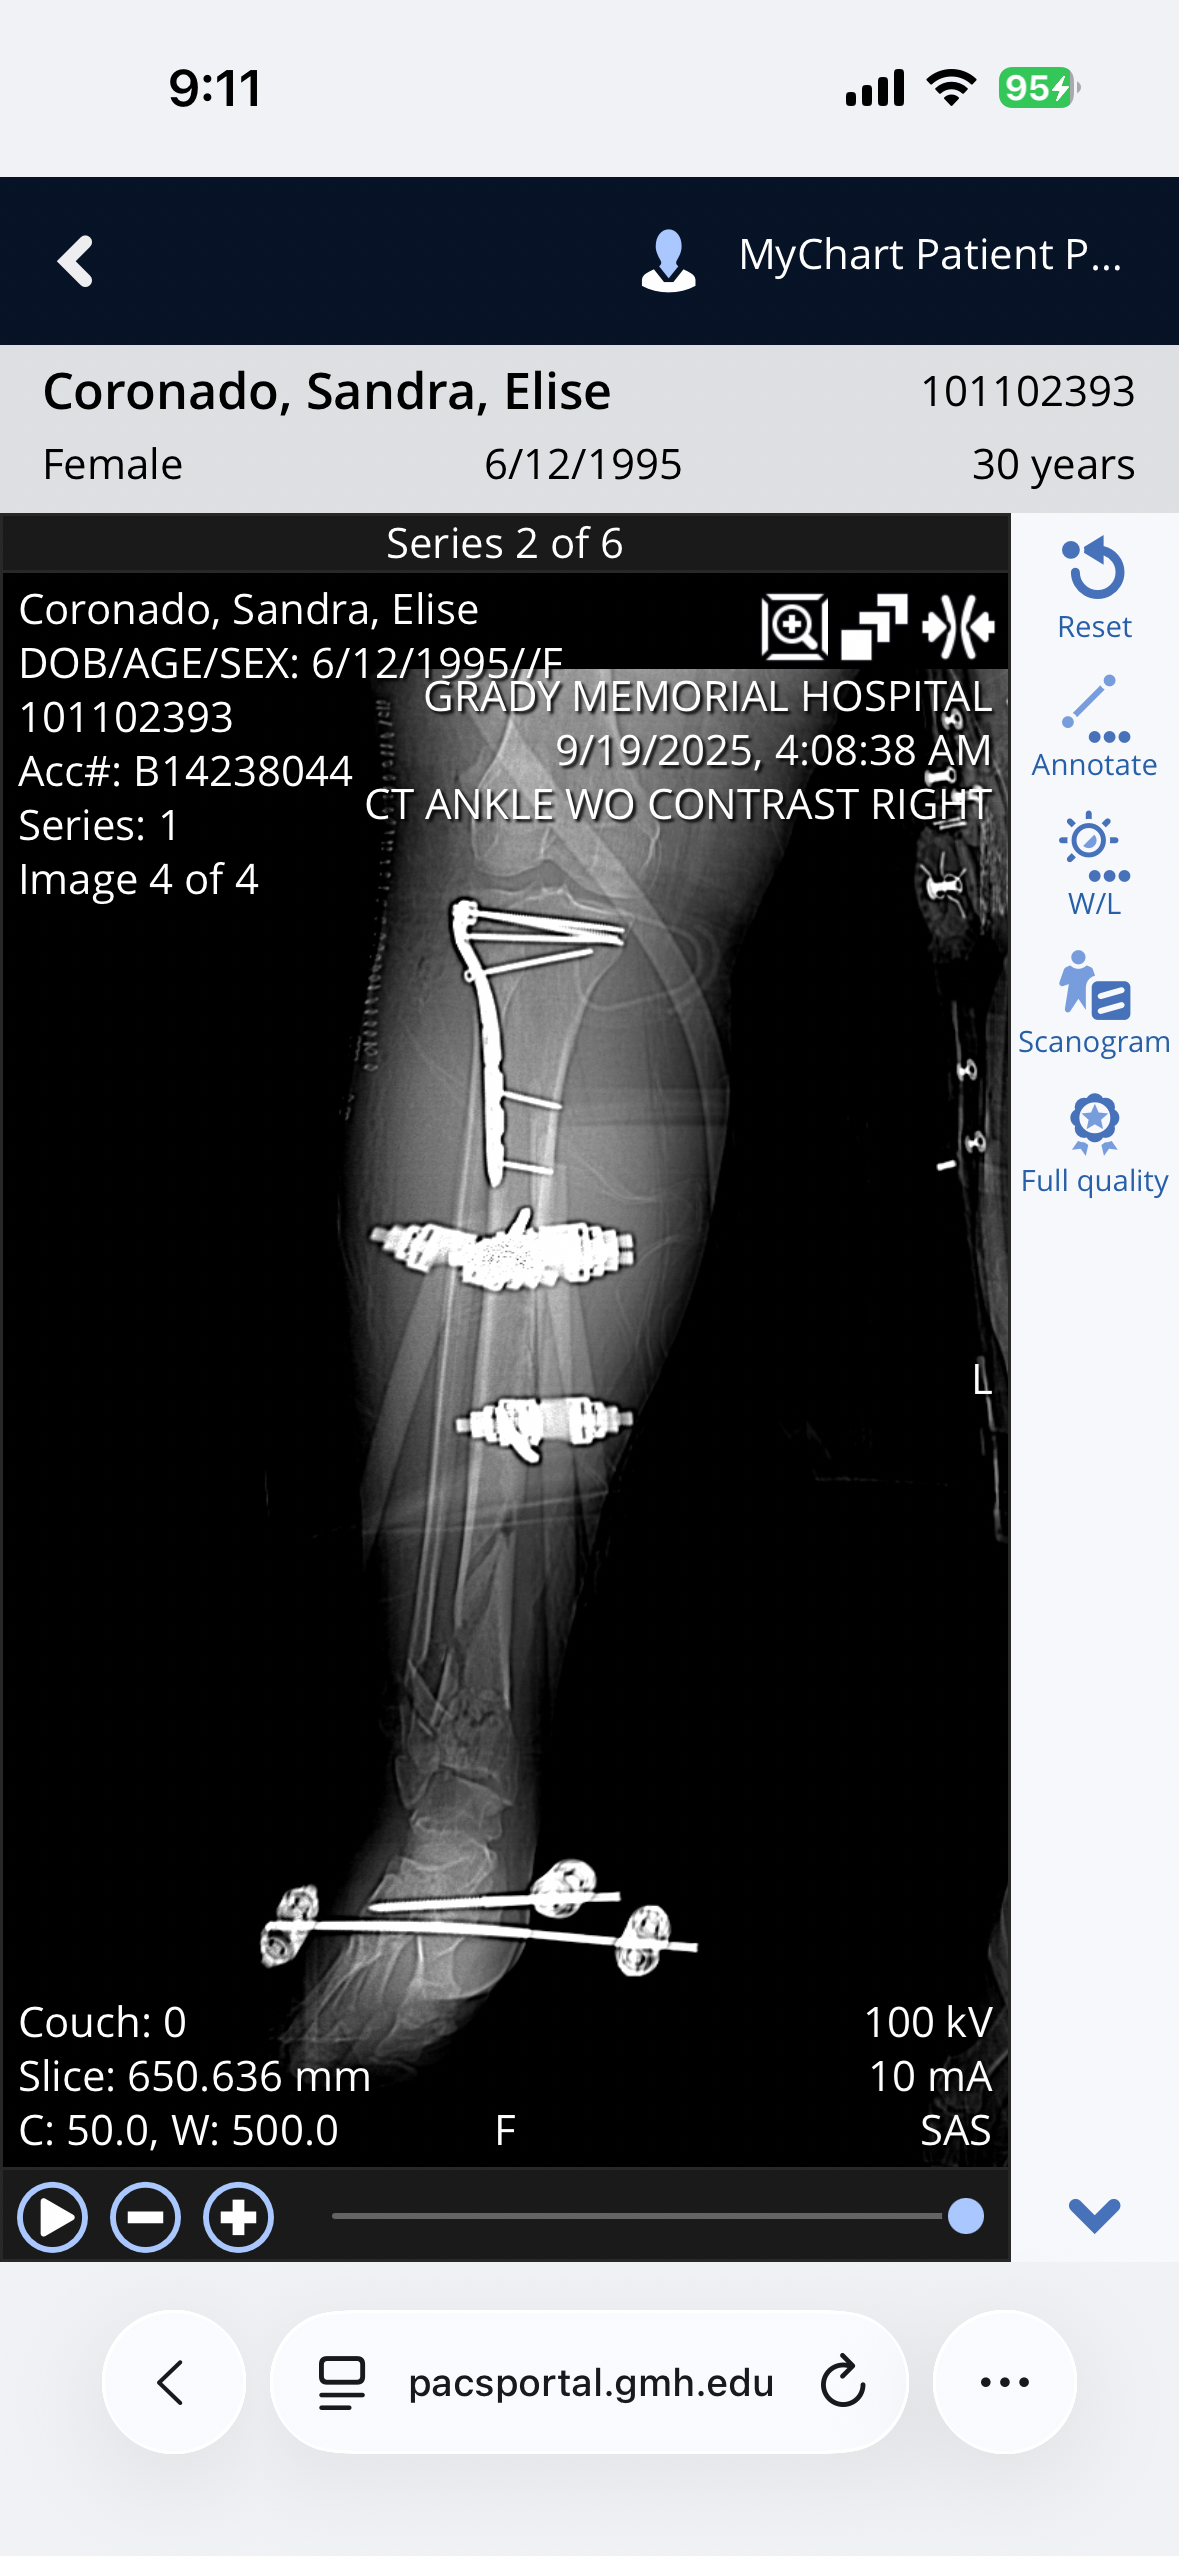

Hi, my name is Sandra I am 30 years old and I got into a motorcycle accident on September 17th. I was going the speed limit, I had the right way, and a woman pulled out in front of me trying to get to the median. I hit her driver side front tire at about 40 to 45 mph. I flew over her car and landed and slid. I was awake through the whole thing. I shattered my right ankle and broke my right tibia. My left ACL was tore and I broke a bone in my left knee. My right wrist was shattered and I have a couple of bones broken in my hand, my left elbow was dislocated. Ligaments were torn and a bone is broken. I can’t walk and I can’t use my arms for anything. I have fallen through all of the medical cracks for my insurance to cover what I need. I have a lot more cost than what I’m asking for but honestly anything helps. I’m going to need someone to care for me while my husband is at work. The doctors estimate about three months before I can even start rehabilitation therapy. I still have another surgery on my right leg and my left leg. My insurance does not cover in-home care and my insurance won’t cover the rehabilitation therapy. I used to work three jobs, two of which required very detailed work with my hands and sadly I’m not sure if I’ll ever be able to do that again. The doctor also mentioned that I may never have full function of my right hand or my right leg due to bones being shattered and broken in the manner that they were.